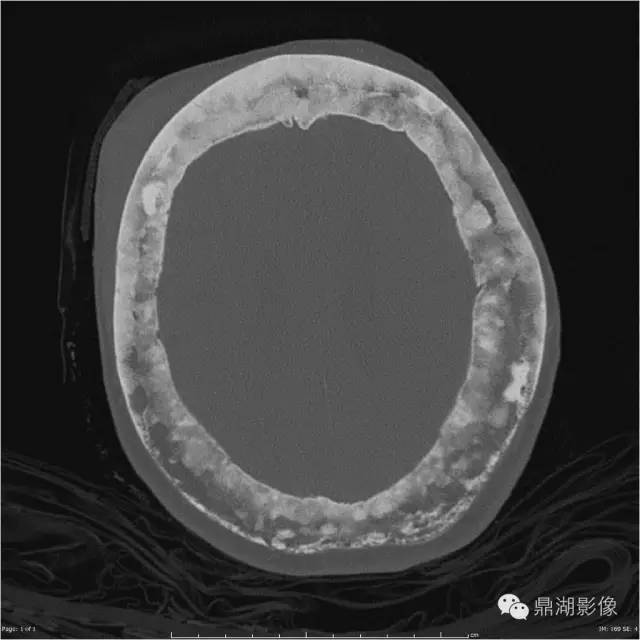

棉絮征—佩吉特骨病

棉絮征

今天下班回家的路上看到一个买棉花糖(Cotton candy)的摊子,回来的时候就想到写一下“Cotton wool”这个征象,典型的棉绒征在国内应该不算常见,今天讲到的棉絮征是Paget(佩吉特)骨病中局限性钙质沉着在疏松的颅骨骨质中呈类似棉絮样改变的征象。

影像特点

随着时间的推移病变可发生变化,治疗后溶骨区域可逆转。则某些特殊区域佩吉特骨病可出现特征性的改变,如脊柱受累时可出现“窗户框”现象,骨盆受累时可出现髋臼内陷及骶髂关节关节强直,颅骨受累时可出现骨质疏松性局限性钙质沉着和颅底凹陷症。

MR、CT 有助于评估脊柱、骨盆、颅骨的佩吉特病变及恶变的情况,PET 则可评估有恶变倾向的病灶。当影像学诊断存在困难或者怀疑佩吉特病有肉瘤变时则需要行穿刺活检。